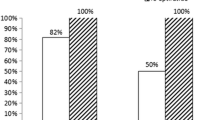

Thrombolysis in MI (TIMI) flow grade 3 was found in 96.7% and 63.3% of the patients of the PBSG and CDSG, respectively (P = 0.005). The results of the PBSG and CDSG are respectively shown as follows: 0% versus 30% no-reflow or slow flow (P = 0.002); 90% versus 66.7% ST-segment resolution ≥ 50% (P = 0.028); 35.6 ± 14.5 frames versus 49.18 ± 25.2 frames on corrected TIMI frame count (P = 0.014); and 60% versus 20% myocardial blush grade 3 (P = 0.001). At 1 month, the major cardiovascular adverse event (cardiovascular mortality) rate was 3.3% in both groups; at 1 year, the rate was 3.3% and 6.7% for the PBSG and CDSG, respectively (P = 1.00). In the CMR subset of cases, the presence of microvascular obstruction (MVO) was detected in 6.7% and 50% of the patients in the PBSG and CDSG, respectively (P = 0.023).

The proportion of patients with an immediate TIMI flow grade < 3 was lower in the PBSG than that in the CDSG after stent deployment (3.3% vs. 36.6%, respectively, P = 0.005) (Table 2). The no-reflow proportion of patients was lower in the PBSG than that in the CDSG (0% vs. 30%, respectively, P = 0.002). The corrected TIMI frame count was lower in the PBSG than that in the CDSG (35.6 ± 14.5 vs. 49.18 ± 25.2, respectively, P = 0.014), and more patients in the PBSG had ST-segment resolution ≥ 50% than that in the CDSG (90% vs. 66.7%, respectively, P = 0.028). The percentage of patients who achieved an MBG of 3 was higher in the PBSG than that in the CDSG (60% vs. 20%, P = 0.001).

There was no significant difference in the procedure time, radiation exposure time, or contrast volume between the two groups. The number of bleeding events and clinical end points were also not significantly different between the two groups (Table 2). The result of the subgroup analysis (Fig. 2) showed that male patients (RR = 1.46; 95% confidence interval [CI] = 1.09–1.94), non-thrombectomy (RR = 1.40; 95% CI = 1.05–1.86), high thrombus burden (RR = 1.52; 95% CI = 1.07–2.16), door-to-balloon time < 90 min (RR = 1.81; 95% CI = 1.24–2.64), and non-anterior wall infarction (RR = 2.53; 95% CI = 1.60–4.02) had a lower risk for no-reflow phenomenon, which favors PBSG (P for interaction = 0.07). According to the CMR subset, the PBSG can reduce the incidence of MVO and improve cardiac function (Table 3, Fig. 3).